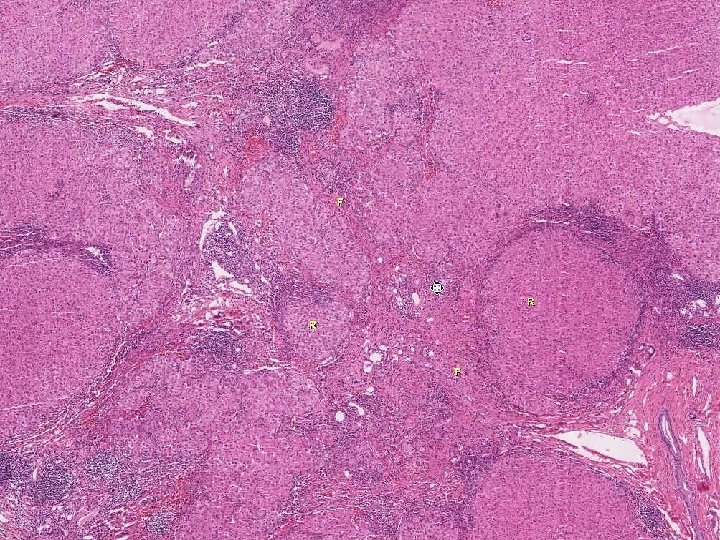

n Alcohol and the Liver Fatty Change n n n Alcohol hepatitis n n n present in over 90% of binge and chronic drinkers liver is enlarged but patient is asymptomatic changes are reversible with cessation of drinking macrosteatosis w/o inflammation or necrosis only between 10 - 15% of alcoholics will develop alcoholic hepatitis may have systemic symptoms and jaundice hepatocellular necrosis with Mallory bodies and PMNs (central hyaline sclerosis) thought to be a precursor of cirrhosis probably more than HALF will go onto cirrhosis if ETOH is not stopped Alcoholic cirrhosis n shrunken nodular liver with uniform small nodules (micronodular cirrhosis)